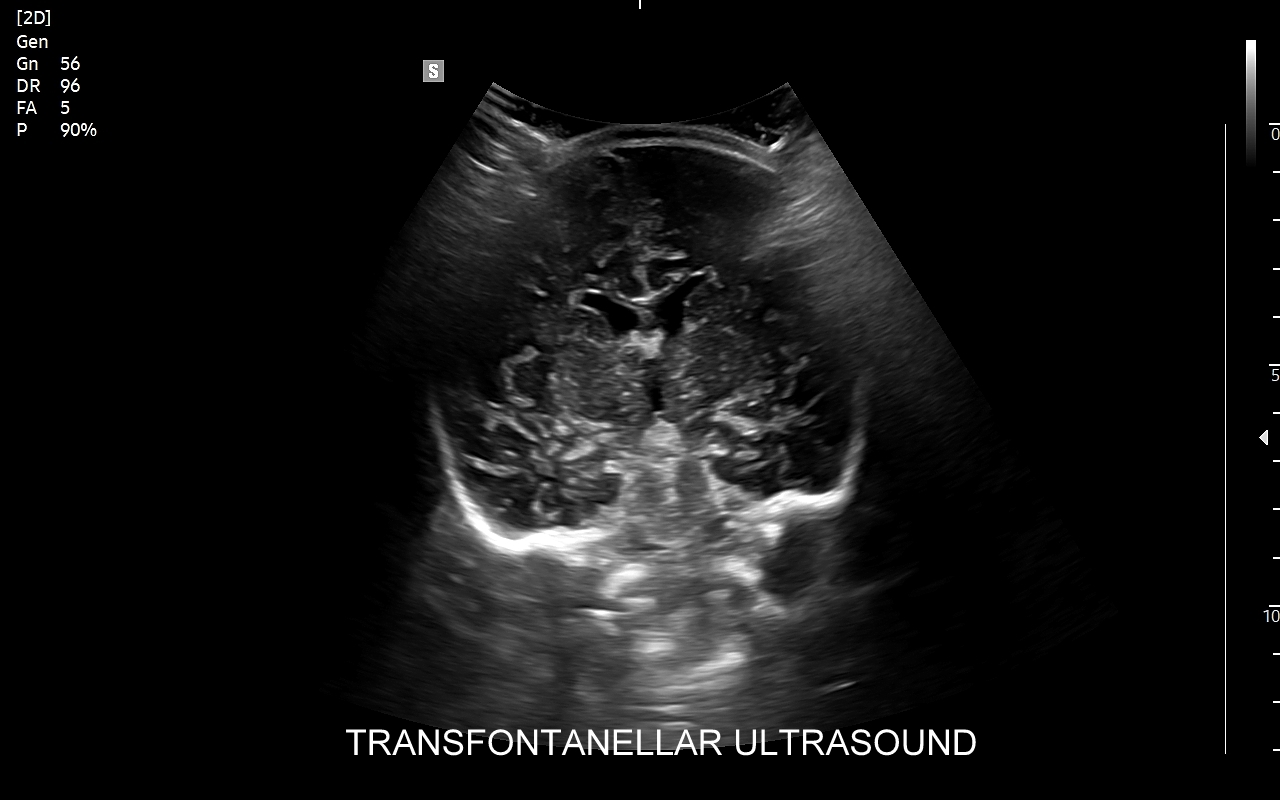

USG główki to podstawowa metoda diagnostyczna mózgu i struktur okołomózgowych u wcześniaków, noworodków i niemowląt. Badanie jest bezbolesne i nieryzykowne w porównaniu do rezonansu magnetycznego, podczas którego dziecko poddawane jest znieczuleniu ogólnemu. Przeprowadzenie szerokiego i szczegółowego badania USG główki jest możliwe aż do momentu zarośnięcia ciemiączka, czyli chrzęstnej struktury w pokrywie czaszki. Ze względu na cienką kość skroniową czaszki dziecka w późniejszym okresie możliwa jest wciąż częściowa ocena mózgowia w badaniu USG. Ambulatoryjne badanie USG przezciemiączkowe zwykle zalecane jest przez neonatologa, pediatrę lub neurologa dziecięcego w celu oceny mózgu wcześniaków, dzieci z małą masą urodzeniową, dzieci po epizodzie niedotlenienia lub krwawienia wewnątrzczaszkowego w trakcie porodu lub okresu noworodkowego, a także w przypadku wystąpienia drgawek, podejrzenia wady układu nerwowego, np. wodogłowia.

W USG główki dziecka oceniane są struktury wewnątrzczaszkowe, tj. mózg wraz z jego układem komór wewnętrznych, sploty naczyniówkowe, istota biała mózgu i obszary jąder podstawy mózgu, morfologia zakrętów i bruzd mózgowia, przestrzeń przymózgowa, a w trybach dopplerowskich wybrane naczynia tętnicze i żylne mózgu, w tym zatoki żylne. Oceniane są również cechy ciśnienia śródczaszkowego. W opisie badania podawane są również wymagane przez neurologa tzw. wskaźniki komorowe oraz wymiary wybranych struktur.